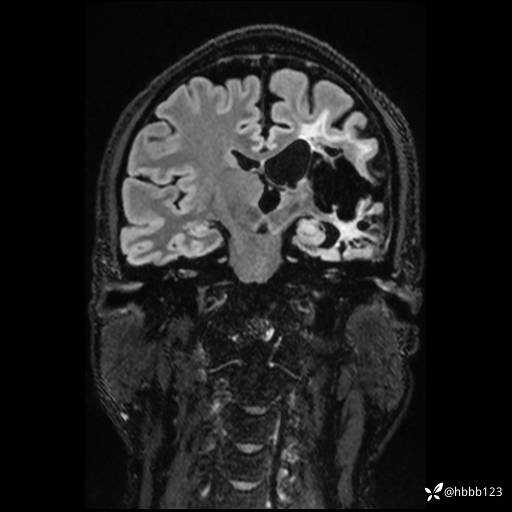

CUBE FLAIR冠状位: